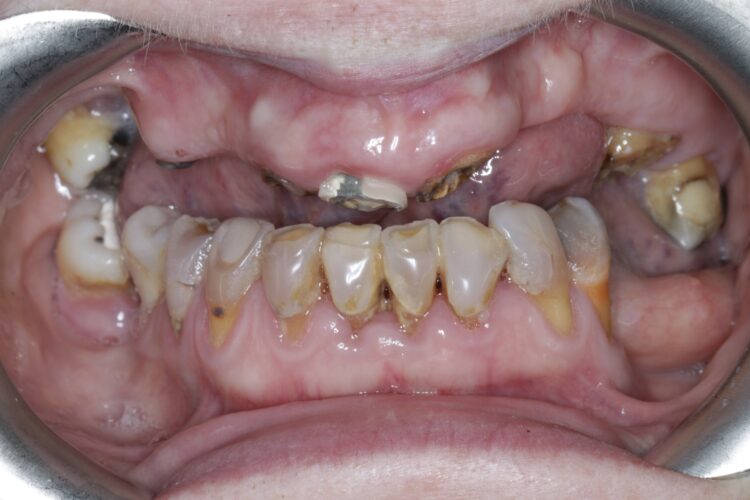

1. Carious roots:

We have all seen those patients that have dark brown/black carious roots down to gum level. Incredibly these roots rarely cause any real symptoms and may persist for years without any problem. You could easily argue that they should be removed, however they are often serving us by preventing bone and soft tissue loss. I will usually only remove these just when I’m ready to place an implant.